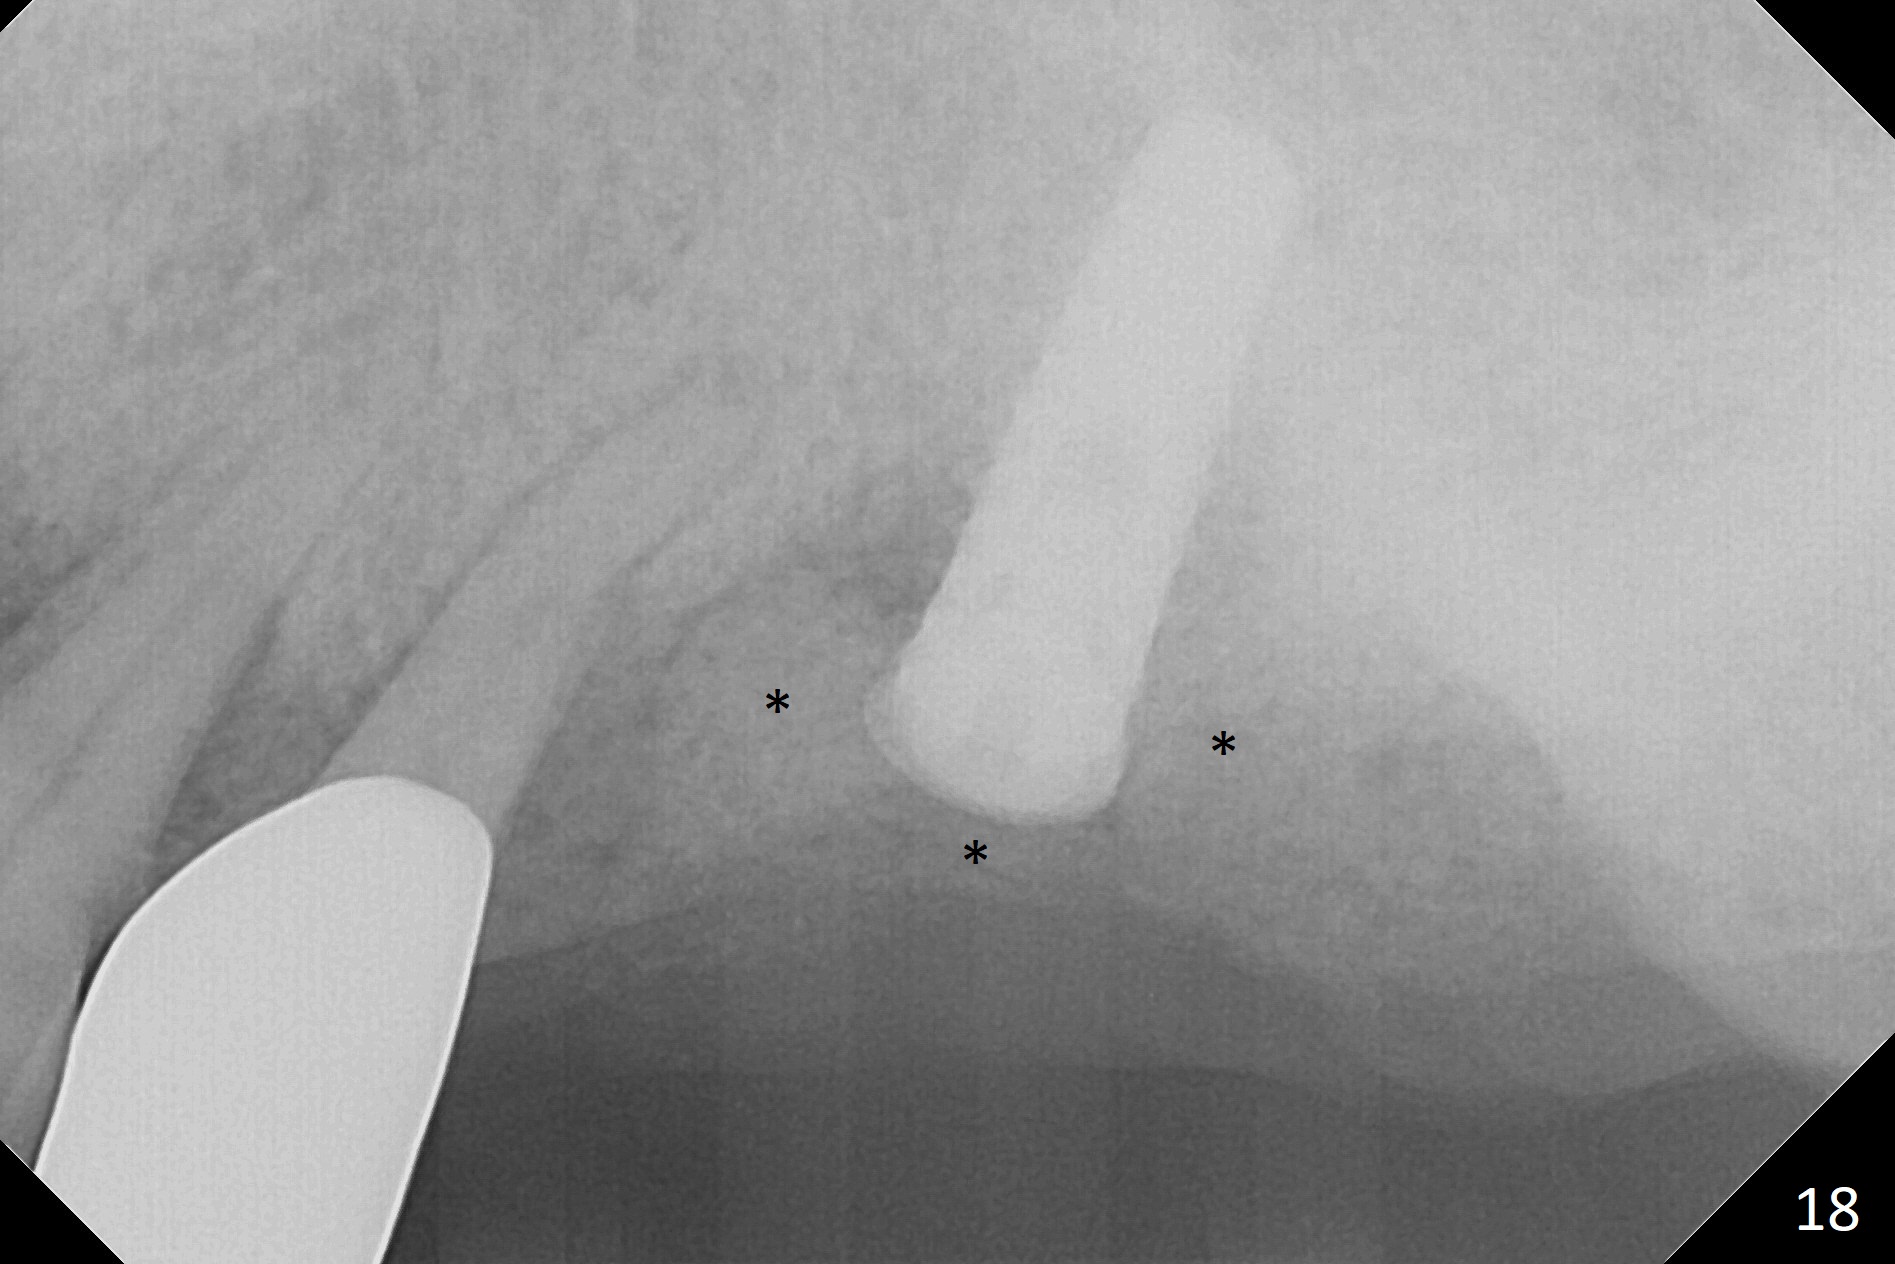

The amount of the bone graft mesial and distal the implant seems to reduce 3 and 4 months postop, respectively (Fig.6,7 arrowheads). When the acrylic is cut off 4 months postop, the bone graft is loose. The gingiva is unhealthy. The abutment and implant are loose. A healing abutment is placed (5x4 mm). The implant is torqued to 35 Ncm 6 months postop with the healing abutment reapplied. The patient will return for follow up nearly 9 months postop. A larger healing abutment will be used if the implant is stable. Two weeks later, use a smaller restorative abutment for easy impression. In fact the implant is unstable with #15 mesial shift due to abnormal occlusion with #17 (Fig.8). Bone density around the implant is low (* in Fig.9 (PA), 10,11 (CT sagittal, coronal sections)). A healing screw is placed for self healing. A 2nd option is to remove the implant (Fig.12), BEB (Fig.13) and place the implant deeper (Fig.14) or larger one (5.5-6.5x13 mm). The 3rd option is to place larger and longer implants (Fig.15 (tapered), 16 (cylindrical)). The implant access has partially closed 14 months postop, but there is a small buccal opening with sanguine exudate. Incision reveals severe bone loss around the implant; the mobile tooth #15 is extracted (Fig.17). After debridement and irrigation with normal saline, Vera Graft (Fig.18 *) and Collagen plug are placed with periodontal dressing.